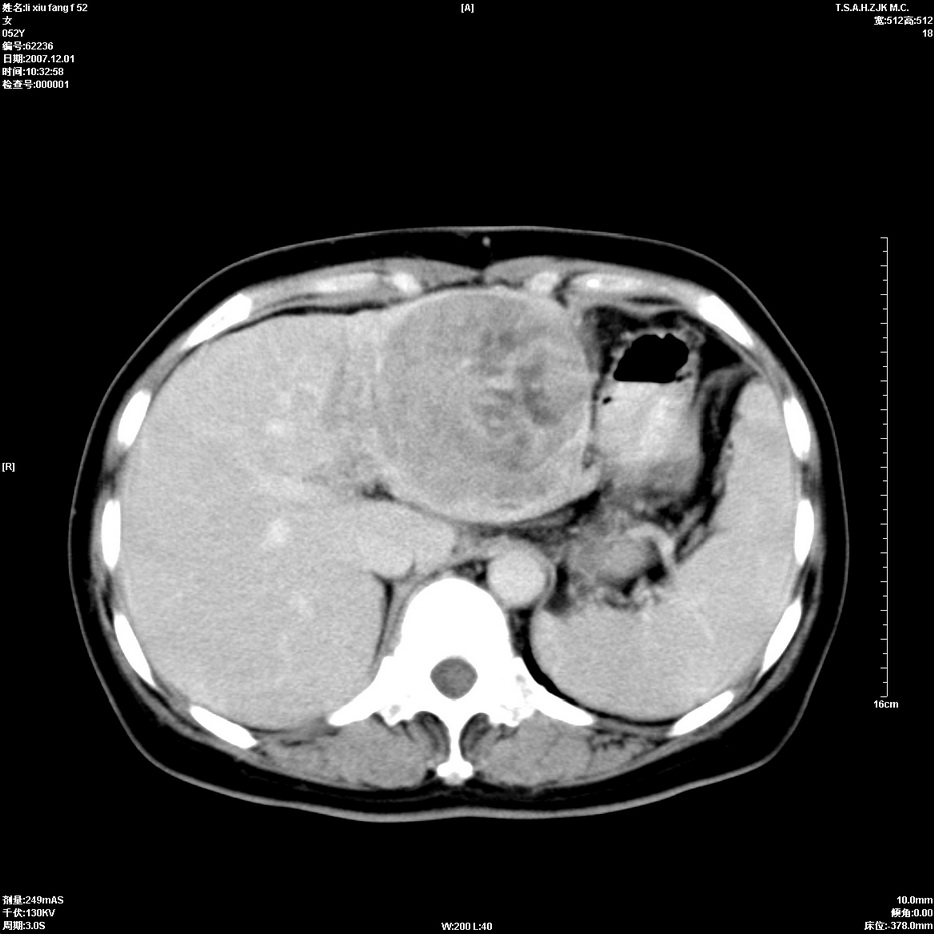

标题: CT12858:女,52岁,胎甲球蛋白861肝左叶占位,肝癌。下腔静 [打印本页]

标题: CT12858:女,52岁,胎甲球蛋白861肝左叶占位,肝癌。下腔静

肝左叶巨大低密度灶肿块,增强符合快进快出表现,有动静脉交通支;静脉期,下腔静脉内有充盈缺损,afp明显升高,支持肝癌并下腔静脉癌栓形成。

支持楼主   门静脉主干及左支癌栓形成

以下是引用拾荒者在2008-4-15 22:57:00的发言:[br]肝左叶巨大低密度灶肿块,增强符合快进快出表现,有动静脉交通支;静脉期,下腔静脉内有充盈缺损,afp明显升高,支持肝癌并下腔静脉癌栓形成。